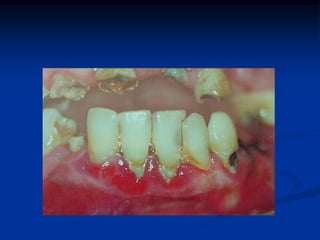

EXAME CLÍNICO INTRA-BUCALLesão inicial de cárie (sem cavitação)

COROA: lesão branca com superfície opaca, rugosa

EXAME CLÍNICO INTRA-BUCALLesãoinicial de cárie (sem cavitação)

COROA: lesão brancacom superfície opaca, rugosa